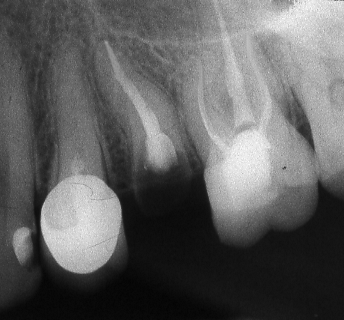

Ендодонтията е раздел от съвременната дентална медицина, който раздел изучава физиологията и патологията на вътрешната част на зъба - пулпна кухина и коренови канали. Названието на раздела идва от старогръцки - ендос - представка за вътрешност и одонтос - зъб. Това е една от научните дисциплини, които претърпяха голямо развитие през последното деситилетие.